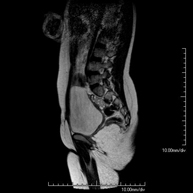

Urinary tract MRI (magnetic resonance urography - MRU)

This non-invasive diagnostic procedure uses an electromagnetic field and radio waves (from a transmitter and receiver) to acquire high-definition anatomical images of the urinary tract. It is a radiation-free procedure. It requires the use of paramagnetic contrast (gadolinium), which is excreted through the urinary system, facilitating 2D and 3D renderings.